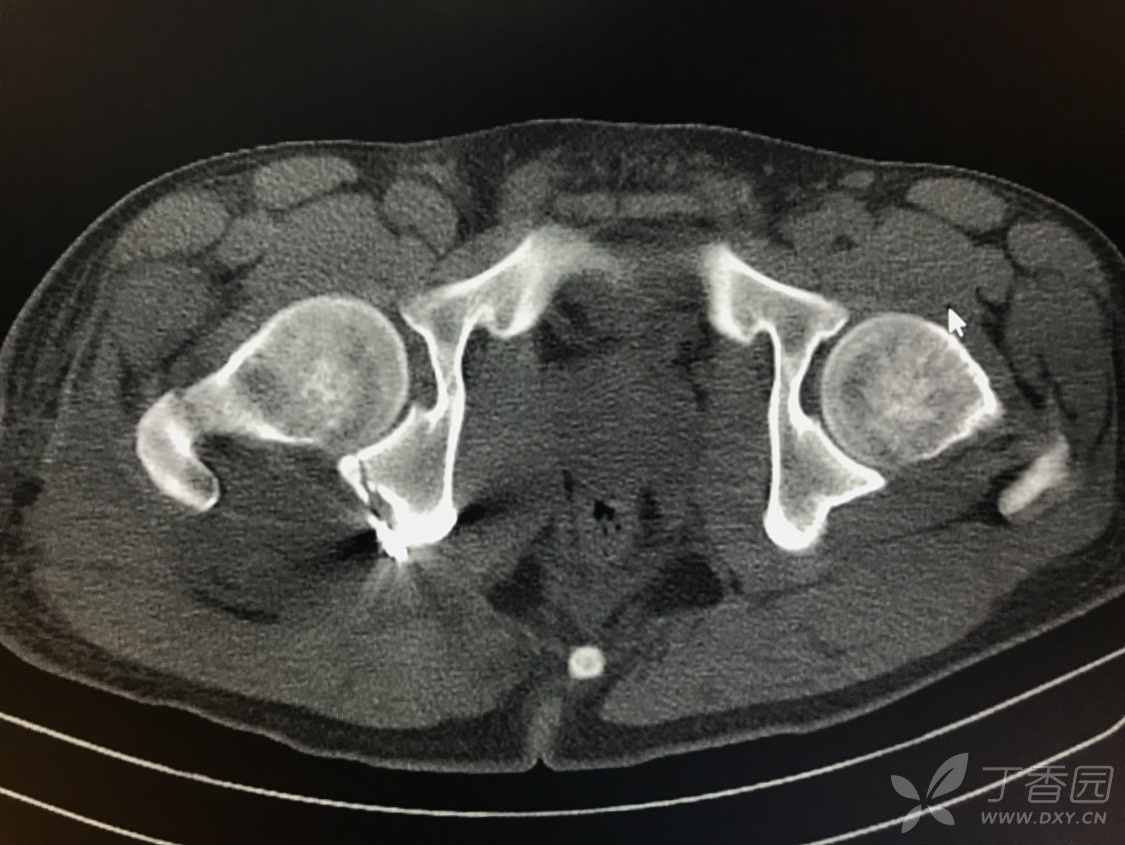

骨盆粉碎性骨折

骨盆粉碎性骨折,跟骨粉碎性骨折

骨盆粉碎性骨折 治疗

髋臼后壁粉碎性骨折

骨盆髋臼粉碎性骨折 非手术治疗

骨一科骨盆粉碎性骨折患者手术纪实

骨盆粉碎性骨折 失血性休克患儿抢救过程